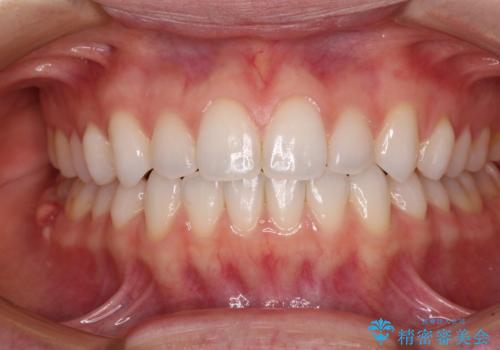

- 上下の前歯の反対咬合を気にして来院された患者様です。

インビザラインを用い、下顎はIPR(歯と歯の間を削る)と歯列全体を後方に移動させ、上顎は前歯を持ち上げることで、反対咬合を改善していくこととしました。

インビザラインによる反対咬合の改善は、上の歯が下の歯を乗り越えていく期間に咬み合わせが非常に不安定となり、治療が長期化することがあります。

こちらの患者様も、一時的に前歯でしか咬めない時期がありましたが、比較的早く咬み合わせが安定し、1年ほどで治療を終えることができました。